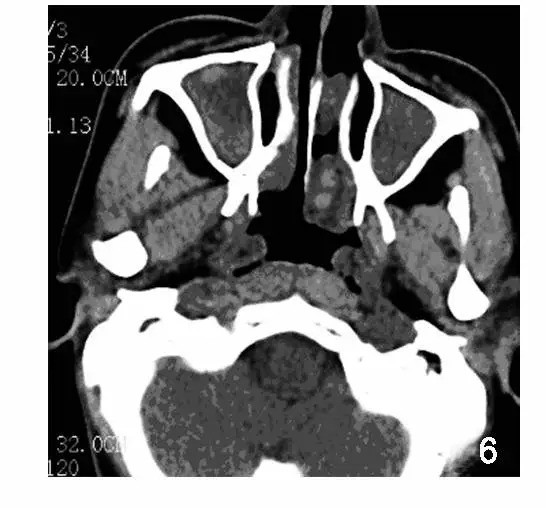

我们抱着猜测的心态去老黄科室的 HIS 系统查了一波,头部 CT 结果显示患者有鼻窦慢性黏膜增厚伴副鼻窦炎。

鼻旁窦 CT:全组副鼻窦炎,左侧鼻腔斑片状软组织密度影,右侧下鼻甲肥厚。(图源:参考文献 2,非本病例)